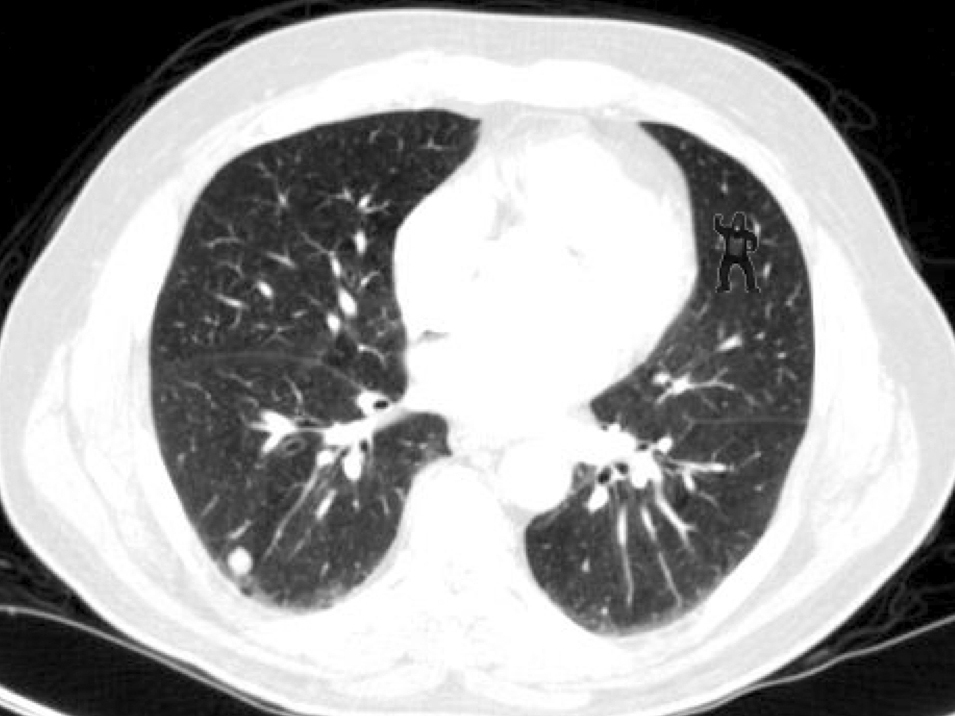

Gorilla lung